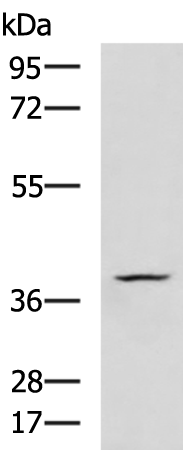

分类: 科研抗体货号: P11089别名:应用: WB,IHC反应种属: Human, Mouse, Rat

分类: 科研抗体货号: P11103别名: 123F2; RDA32; NORE2A; RASSF1A; REH3P21应用: WB,IHC反应种属: Human, Mouse